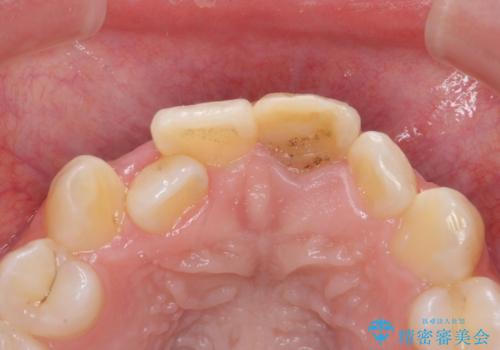

前歯の見た目が気になる。

- 前歯の見た目が気になるとの事で来院。

根の治療のやりかえは希望されなかったので土台だけやりかえを行い、ジルコニアクラウンで治療を行いました。

綺麗な被せ物が入り大変満足して頂けました。